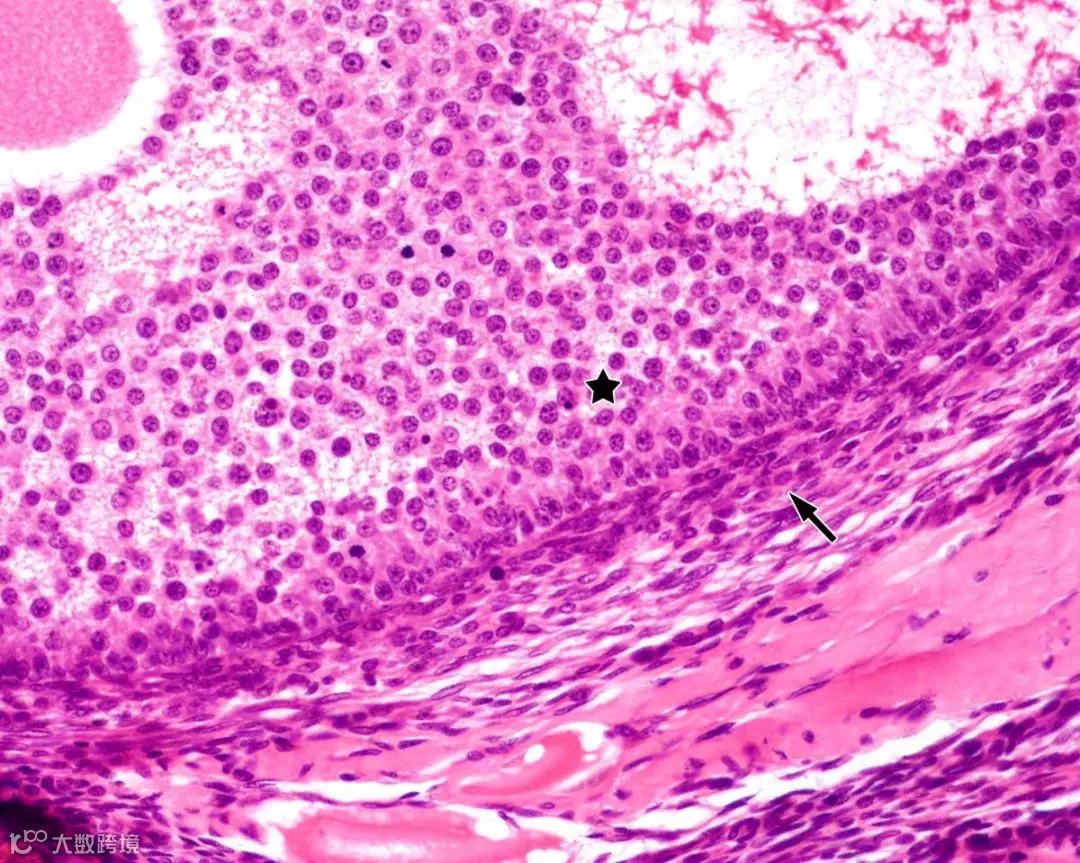

△ 显微镜下的卵巢颗粒细胞

颗粒细胞是一种卵巢合成和分泌抑制素、雌激素的主要功能细胞,在女性卵泡的生长、发育和成熟,黄体生成等方面发挥着重要作用。